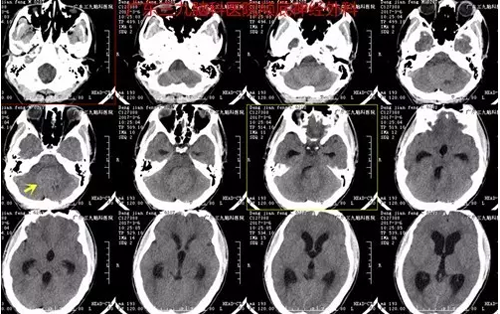

邓某,于2017年3月5日入院,患者诉2周前无明显诱因间断出现头晕头痛,通过相关检查,诊断:小脑蚓部占位性病变。完善术前检查,3日后行“小脑蚓部占位性病变切除术” ,术中肿瘤全切,术后恢复良好。术后诊断:小脑蚓部髓母细胞瘤。

图1:术前CT提示四脑室-小脑蚓部一团块占位性病变